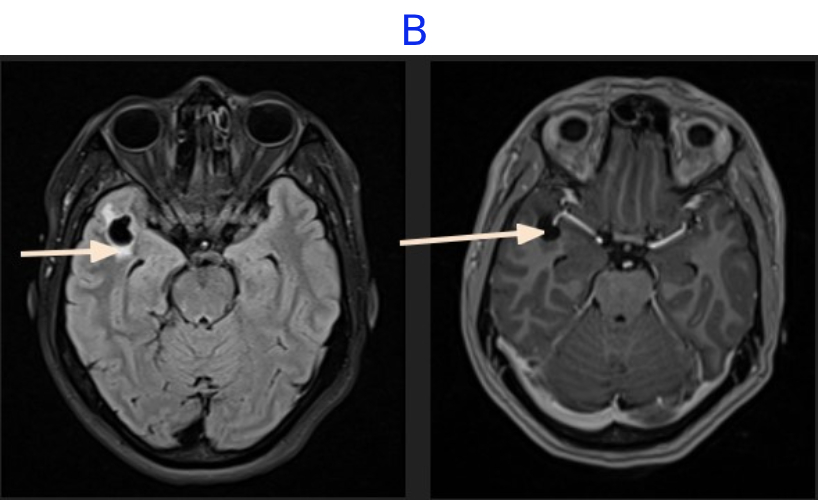

C. FINDINGS - MR BRAIN

• C. No diffusion restriction in DWI